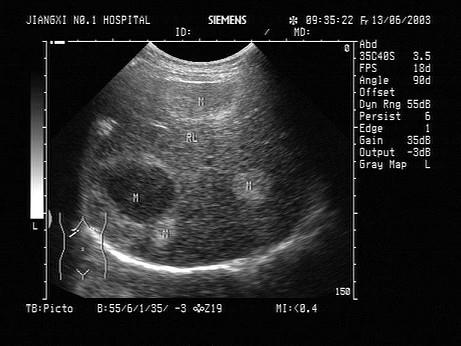

男,48岁,上腹隐痛,有胃病史。结合超声声像图,最可能的诊断为?(?)A.肝包虫病B.肝多发性血管瘤C.肝癌D.脂肪肝E.肝囊肿

问题 男,48岁,上腹隐痛,有胃病史。结合超声声像图,最可能的诊断为?(?)

选项 A.肝包虫病 B.肝多发性血管瘤 C.肝癌 D.脂肪肝 E.肝囊肿

答案 B